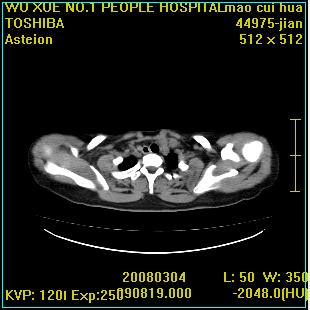

标题: CT12025:男,50岁,左肩活动受限半年。 [打印本页]

标题: CT12025:男,50岁,左肩活动受限半年。

肩关节骨质破坏呈小囊状,其周软组织轻度肿胀,余未见异常。

考虑:肩袖损伤。建议mri。

左侧肱骨头密度不均匀,高低混杂,周围软组织略肿胀,考虑结核性病变。

左侧肱骨头密度不均匀,高低混杂,髓腔密度稍高,周围软组织略肿胀,肌间隙模糊,考虑慢性骨髓炎可能。密切结合临床!

肩关节周围软组织轻度肿胀,肌间隙模糊,余未见异常。

考虑:肩周炎。